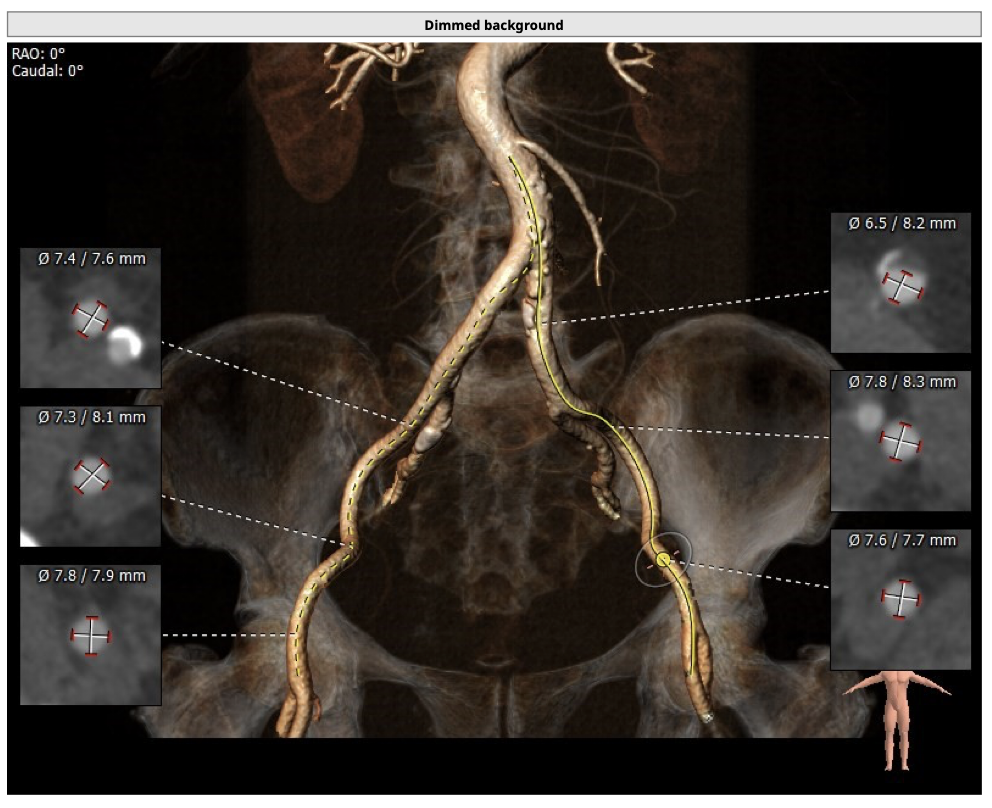

主动脉CT

制定策略:

经分析研判,拟从右侧股动脉穿刺入路,结合患者返流特点与主动脉根部结构,选用L26号的VenusA-Valve瓣膜,使用VenusA-Plus可回收输送系统,确保手术安全和瓣膜的稳定释放,必要时可使用圈套器辅助瓣膜释放,瓣膜释放后结合造影和超声情况,决定是否后扩。